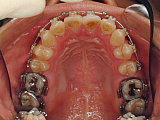

初診時の状態です。上下の歯並びがガタガタしています。

| まず上下の奥歯をゆっくりと後方に移動していきます。 |

奥歯の位置を調整しながら前歯にも装置を付けていきます。

歯列内にスペースができています。 |

| できたスペースをうまく利用して前歯を並べていきます。 |

歯を抜かない矯正ですべての歯を並べることができました。 |